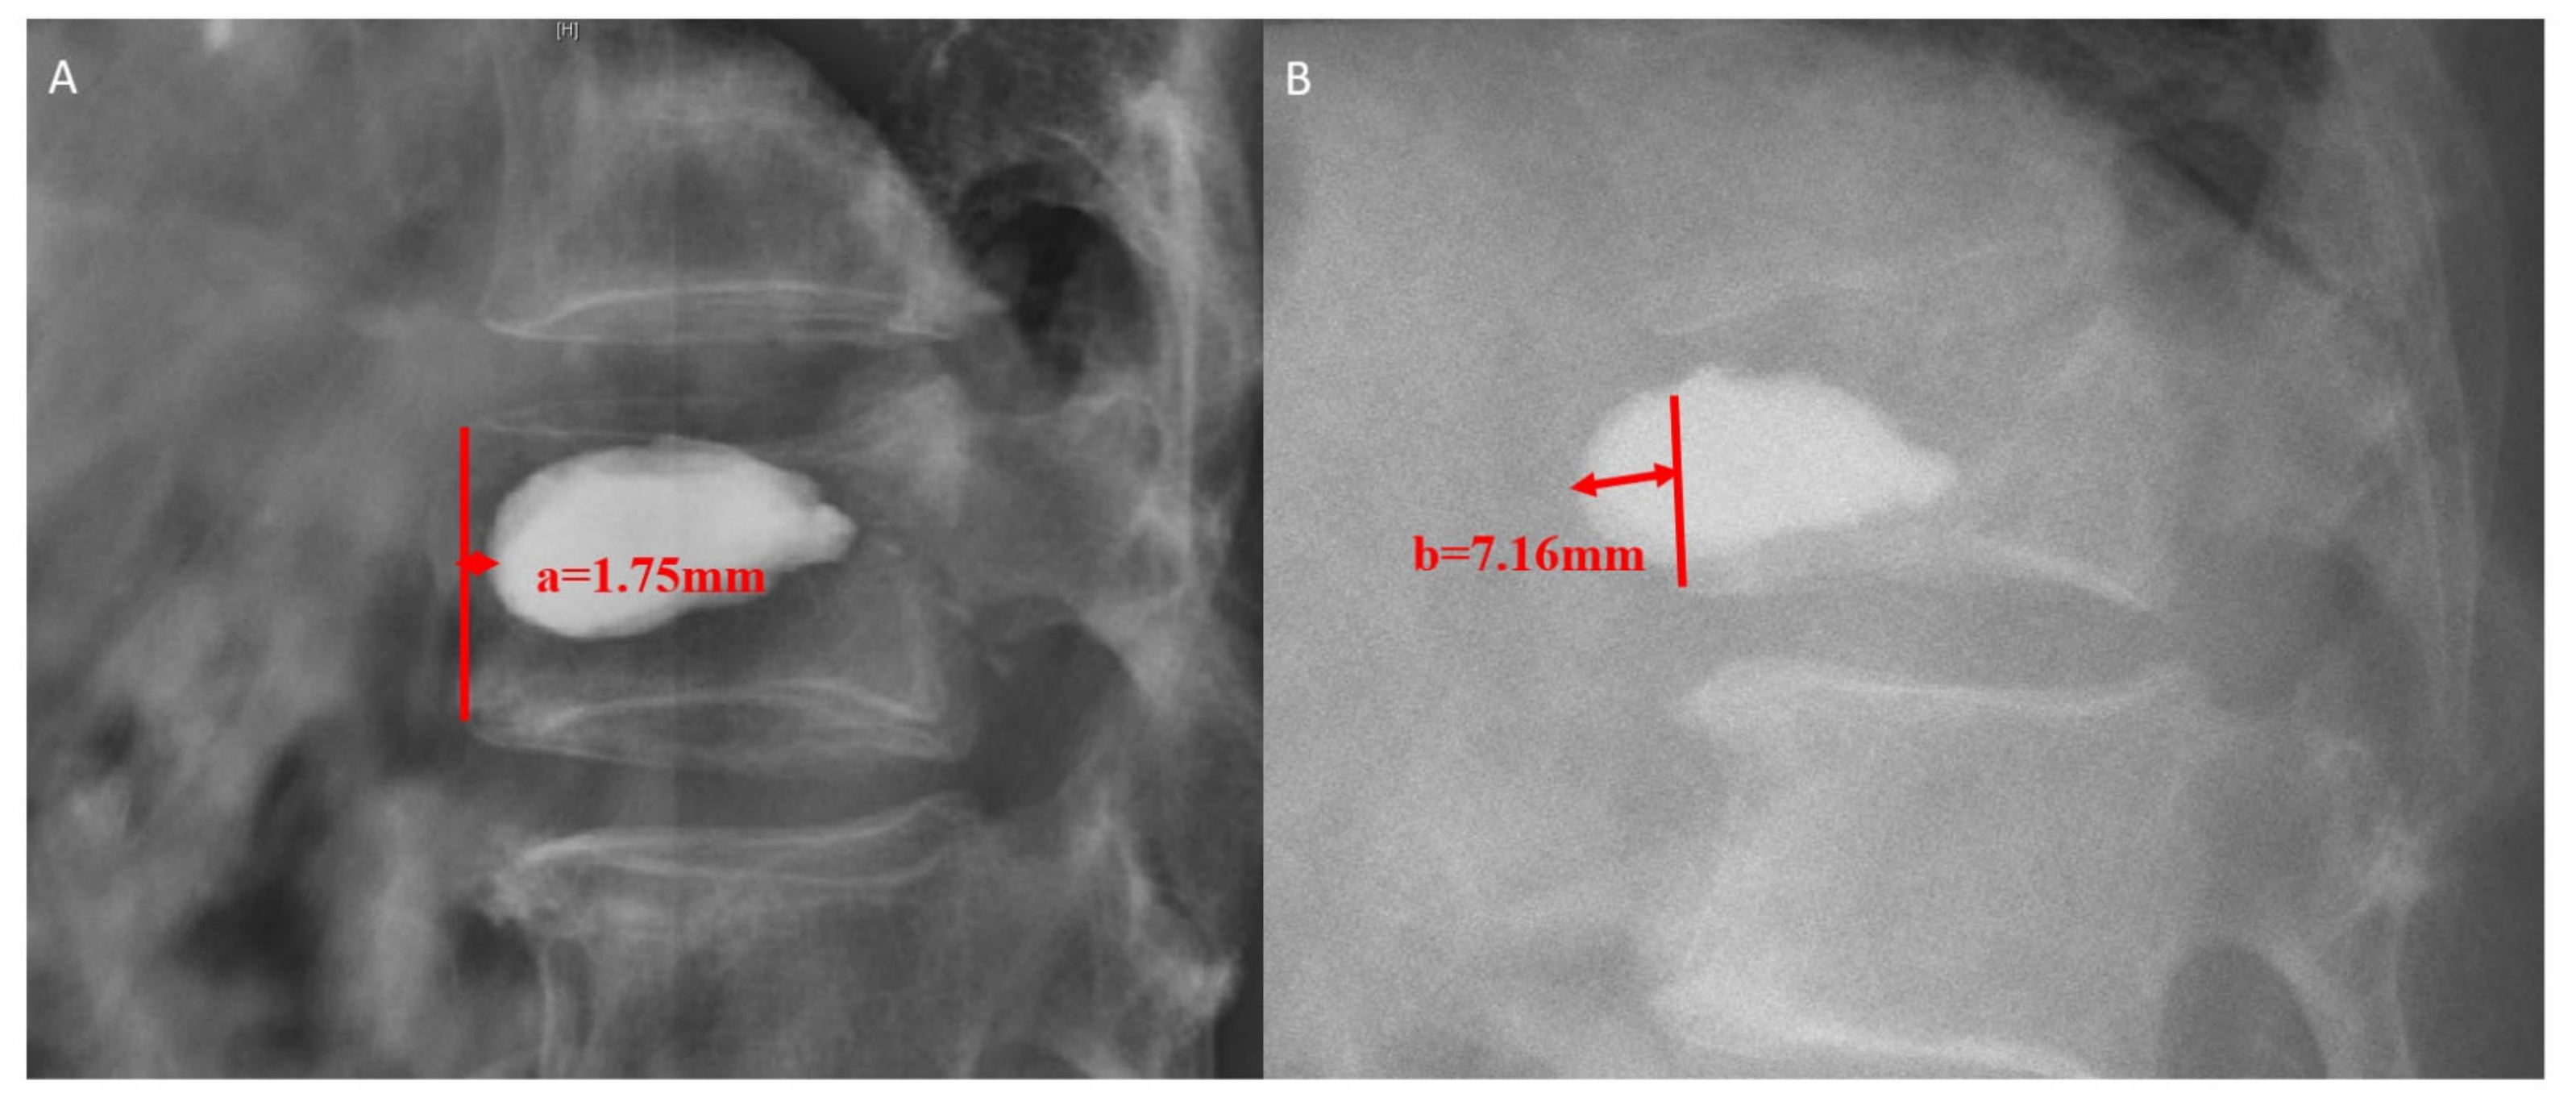

- Liu, J.; Tang, J.; Liu, H.; Gu, Z.; Zhang, Y.; Yu, S. A novel and convenient method to evaluate bone cement distribution following percutaneous vertebral augmentation. Sci. Rep. 2020, 10, 16320. [Google Scholar] [CrossRef]